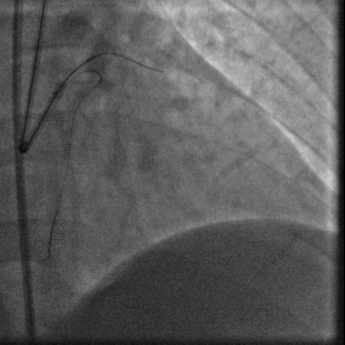

冠脉造影:

右头